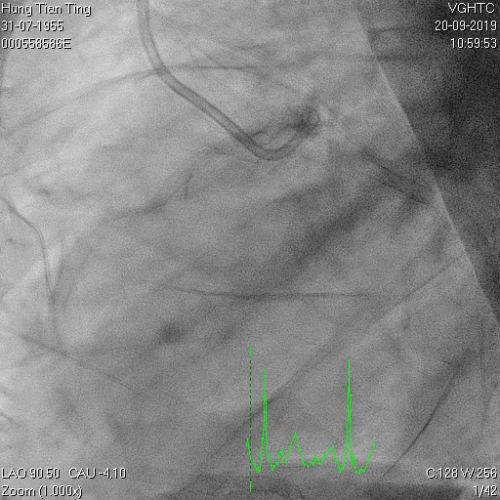

A 64-year-old male with a history of hypertension, chronic renal disease (stage 3), and right lower limb PAD with critical limb ischemia had received PTA twice in 2018. He also had CAD, TVD, with NSTEMI in 2018 and had undergone PCI for RCA, LAD and LAD in 2018 and 2019. Due to under-expanded mid-LAD stent, he subsequently underwent PCI several times due to recurring ISR. The diagnostic angiogram in September 2019 is shown in Figures 6a and 6b and the under-expanded stent was still not dilatable (figures 7a and 7b) using high-pressure non-compliant balloons. He subsequently underwent treatment with contrast-facilitated excimer laser. After diagnostic OCT and balloon predilatations, the lesion was treated with a 0.9mm laser catheter (X80) at 80 mJ/mm2 and 80 Hz 4 times in total, facilitated by 1:1 diluted contrast medium. However, it remained undilatable despite raising the pressure of the NC balloon to 30-35 atm (figures 8a and 8b). We switched to a 1.4mm laser catheter. However, this created local vessel perforation due to non-coaxiality, which was finally sealed off by prolonged balloon occlusion (figure 9a and 9b). Further NC balloon dilatation inadvertently increased the pressure to more than 35 atm, which ruptured the balloon and resulted in a powerful jet perforating the vessel wall proximal to the lesion (figure 10), followed by massive exudation and tamponade. Fortunately, the patient was stabilized by prolonged BC occlusion and pig-tail drainage of the pericardial blood (figure 11a and 11b). Post hoc review of the diagnostic OCT did show lack of circular intimal calcification around the under-expanded stent, which was secondary to tight fibrotic band in the vessel wall (Figure 12). The patient was successfully re-treated during another admission with rotational atherectomy, high-pressure balloon dilatation, and DEB, and his postoperative course was uneventful.

Figure 6a and 6b